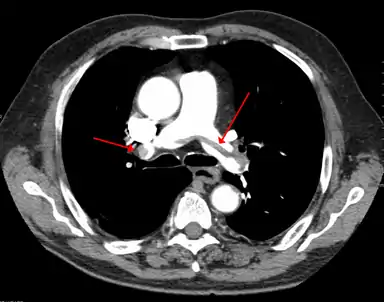

A CT image with red arrows indicating PE (grey) in the pulmonary arteries (white)